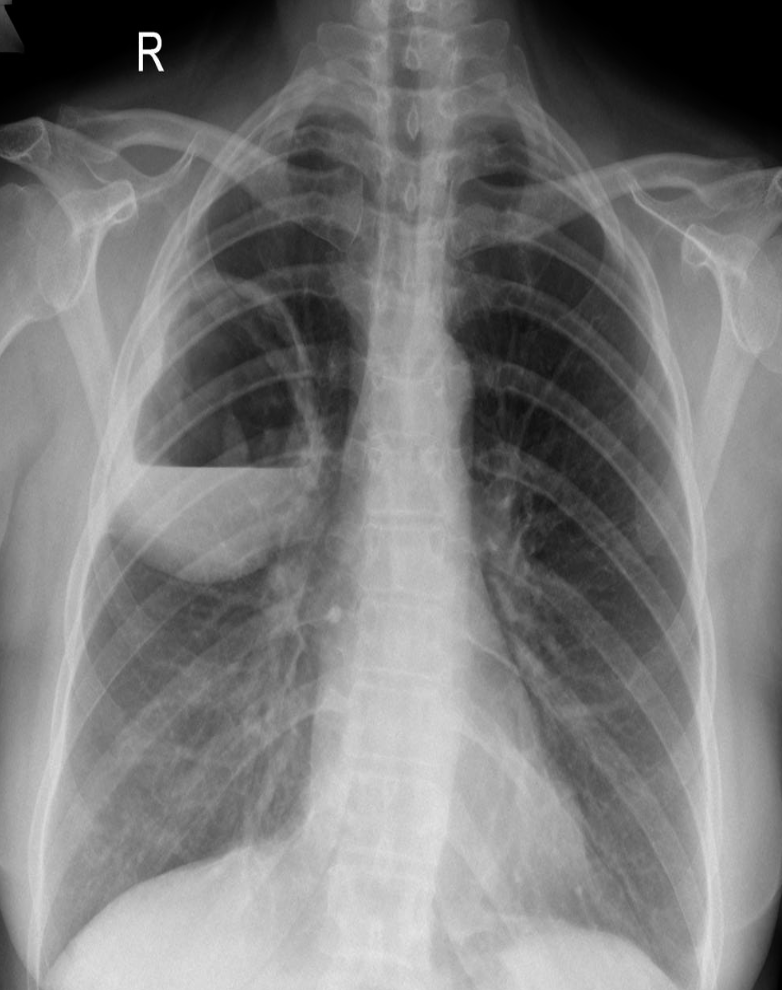

Case 17 Z

40 year old man presented with cough and shortness of breath for six months. Six weeks ago he noticed painful lumps on the skin of his legs which had resolved in two weeks

What is the abnormality in CXR? Hilar lymphadenopathy (enlarged lymph nodes in the hila of both lungs)

-

What is the most likely diagnosis? Sarcoidosis; lump

Bilateral Hilar Lymphadenopathy: Causes

| Category | Causes |

|---|---|

| Sarcoidosis | Sarcoidosis |

| Infection | * Tuberculosis * Fungal infection * Mycoplasma * Intestinal Lipodystrophy (Whipple’s disease) |

| Malignancy | * Lymphoma * Carcinoma * Mediastinal tumors |

| Inorganic dust disease | * Silicosis * Berylliosis |

| Extrinsic allergic alveolitis | * Such as bird fancier’s lung |

| Less Common Causes | * Churg-Strauss syndrome * Human immunodeficiency virus * Extrinsic allergic alveolitis * Adult-onset Still’s disease |